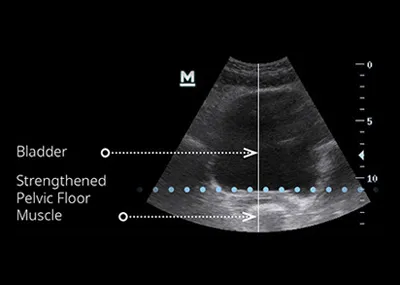

EMsella is a non-invasive treatment that uses high-intensity focused electromagnetic (HIFEM) technology to strengthen the pelvic floor muscles and improve bladder control. While you sit fully clothed on the EMsella chair, the technology delivers thousands of deep pelvic floor contractions—the equivalent of doing 11,000 Kegel exercises in just one 28-minute session.

The Emsella chair uses the same trusted HIFEM technology found in EMsculpt NEO. As you sit fully clothed, electromagnetic energy penetrates deeply into the pelvic floor area, inducing supramaximal pelvic-floor muscle contractions that would be impossible to perform voluntarily. These contractions re-train weak muscles, improve bladder control, and restore confidence.

In a single 28-minute session, the treatment delivers the equivalent of over 11,000 Kegel exercises, which are extremely important in muscle re-education, restoring neuromuscular control and improvement of intimate wellbeing.